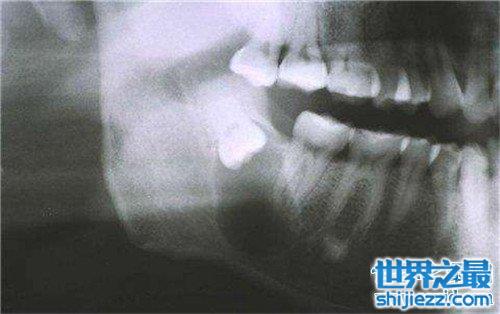

尽头牙,在口腔医学中称"智齿",也叫阻生牙、第三磨牙。它是人类口腔中萌出最晚的一颗牙,往往在18-25岁才萌出。随着人类的进化,由于颌骨变小,而没有足够的位置,从而形成智齿错位萌出。它往往会使牙冠周围软组织产生炎症,即"尽头牙"发炎。这种牙不但无功能反而有害,必须尽早拔除,以防止进一步发炎。人类的恒牙列共有三十二颗牙,其中最后萌出的四颗第三大臼齿,位于上下左右牙弓的最后方,因为萌出在智能成长后十六到廿四岁,所以又有智能齿之称,简称智齿。

然而,由于演化及食物精化,人类的颌骨,因为不再需要强大的咀嚼力而有逐渐变小的趋势,在这变小的颌骨上如要容纳跟以往相同数目及大小的牙齿,则牙跟牙之间往往会有空间不足的问题,于是拥挤,长倒,长弯,或长不出来的情形便发生,这就是阻生。就统计上而言,长不出来的情形最常发生在智齿,所以习惯上常称这种长不出来的智齿为阻生智齿。

智齿的个体差异差异很大,有的年轻时就会出现,还有些人是在中年出现智齿,有的人终生不长,这都是正常的。而且四颗智齿也不是都必然会长全,某些人的智齿可能只长几颗,有的智齿甚至长到一半就不再生长,有的人智齿歪着长,这种情况就称为智齿阻生,严重影响口腔健康,应尽早拔除。